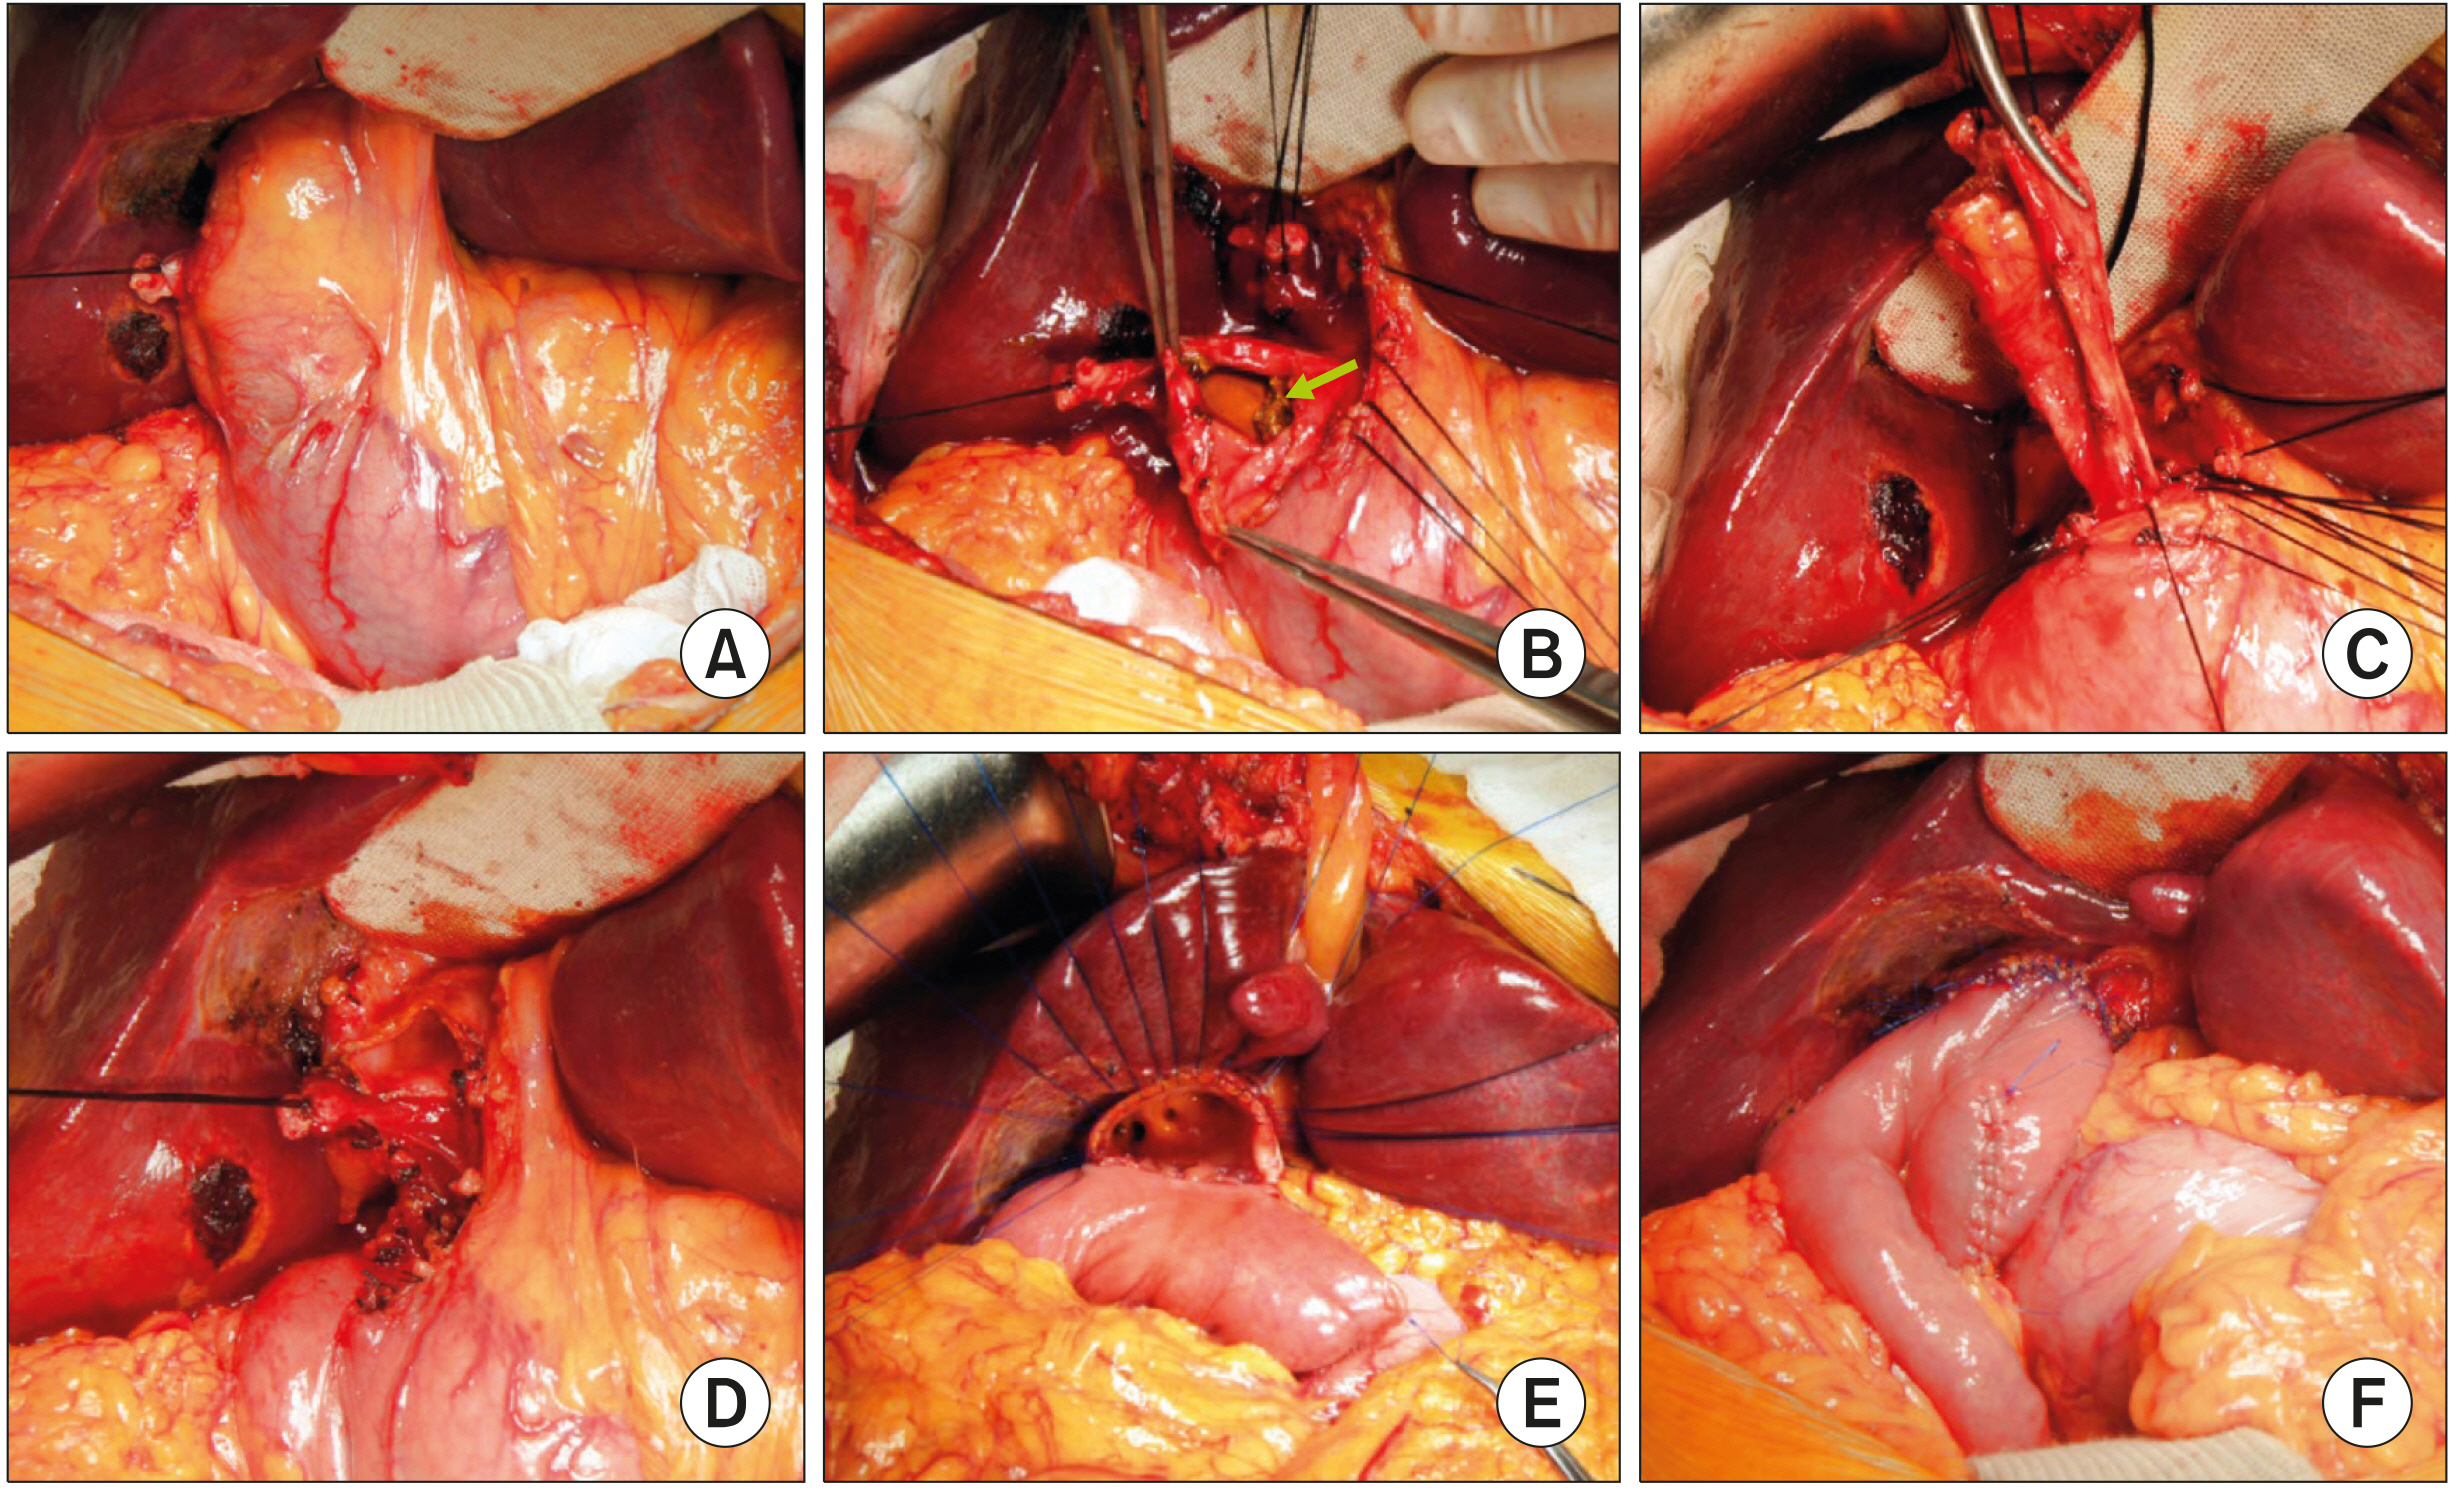

- Despite development in endoscopic treatment and minimally invasive surgery for choledocholithiasis, there remains a small number of patients who require bypass Roux-en-Y choledochojejunostomy (RYCJ) because of the intractable occurrence of common bile duct (CBD) stones. We herein present the detailed procedures of open RYCJ customized for intractable choledocholithiasis. The first method is a side-to-end choledochojejunostomy with intraluminal closure of the distal CBD. This method was applied to a 79-year-old female patient who underwent endoscopic retrograde cholangiopancreatography (ERCP) more than 10 times in the past 14 years (Case No. 1). The distal CBD was explored through choledochotomy and then the distal CBD lumen was occluded with internal running sutures. A large-sized choledochojejunostomy was performed. The patient recovered uneventfully and has been doing well for the past 2 years. The second method is an end-to-end choledochojejunostomy with segmental CBD resection. It was applied to a 75-year-old male patient who underwent ERCP 9 times in the past 10 years (Case No. 2). The CBD was resected segmentally and a large-sized choledochojejunostomy was performed. The patient also recovered uneventfully and has been doing well for the past 2 years. In conclusion, the primary indication of bypass RYCJ is intractable choledocholithiasis which requires numerous sessions of endoscopic stone removal over a long period. Open RYCJ is the preferred procedure to date. If the papilla is patulous, the distal CBD should be occluded or resected to prevent reflux ascending cholangitis. We recommend to resect the intrapancreatic distal CBD if it is markedly dilated like choledochal cyst.